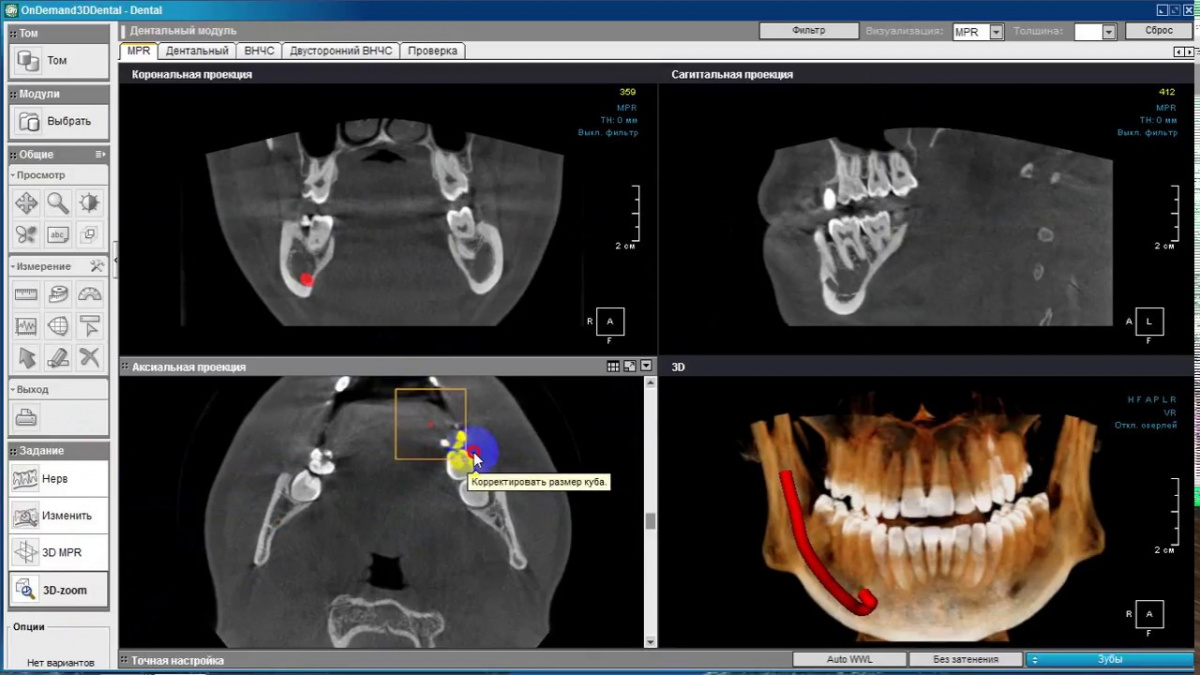

Немаловажным, а может главным вопросом, является универсальность программы-просмотровщика, в которой будут работать врачи-стоматологи. У Papaya 3D есть два варианта программ: Triana и OnDemand3D. Оба просмотровщика обладают схожим интерфейсом и имеют самые важные опции, а именно:

Triana.jpg  OnDemand3D.jpg

• режим MPR (многоплоскостная реконструкция). Именно здесь выстраивается интересующий участок челюсти или зуба для анализа.

• панорамный реформат. Возможность постройки классической и сегментарной панорамы позволяет продемонстрировать план лечения пациенту, а также оценить расположение анатомических структур на боковых кросс-секциях.

• модуль дентальной имплантации. Возможность виртуальной установки дентального имплантата с анализом окружающей костной ткани. В библиотеке представлен широкий спектр имплантологических систем с индивидуальной прорисовкой имплантата.

• выделение нижнечелюстного канала позволяет продемонстрировать расположение важного анатомического образования и определить зону безопасности при проведении лечения.

• функции плотности, линейных измерений и угла – необходимы для получения полноценной информации для последующего лечения.

• 3D режим – показывает трехмерную модель челюсти с целью определения аномалий, деформация, а также визуализации виртуальных имплантатов.

triana3.jpg triana4.jpg triana5.jpg

OnDemand3D (1).jpg OnDemand3D (2).jpg OnDemand3D 1.jpg

Таким образом обе программы являются простыми в пользовании, но обладающими обширным спектром возможностей для диагностики любыми специалистами-стоматологами. В данные программы происходит загрузка классических файлов DICOM 3.0, которые являются общепринятым форматом записи данных пациента. Это важный момент, так как позволяют врачу, имеющему полную версию программы загружать даже сторонние исследования и просматривать их в этих программах. Простота в освоении этих программ позволяет даже специалисту, не работающему раннее с этими программами, быстро адаптироваться и получить качественную информацию. Возможность выгрузки STL-файла дополнительно создает возможность интегрировать данные с цифровым ортопедическим протоколом.